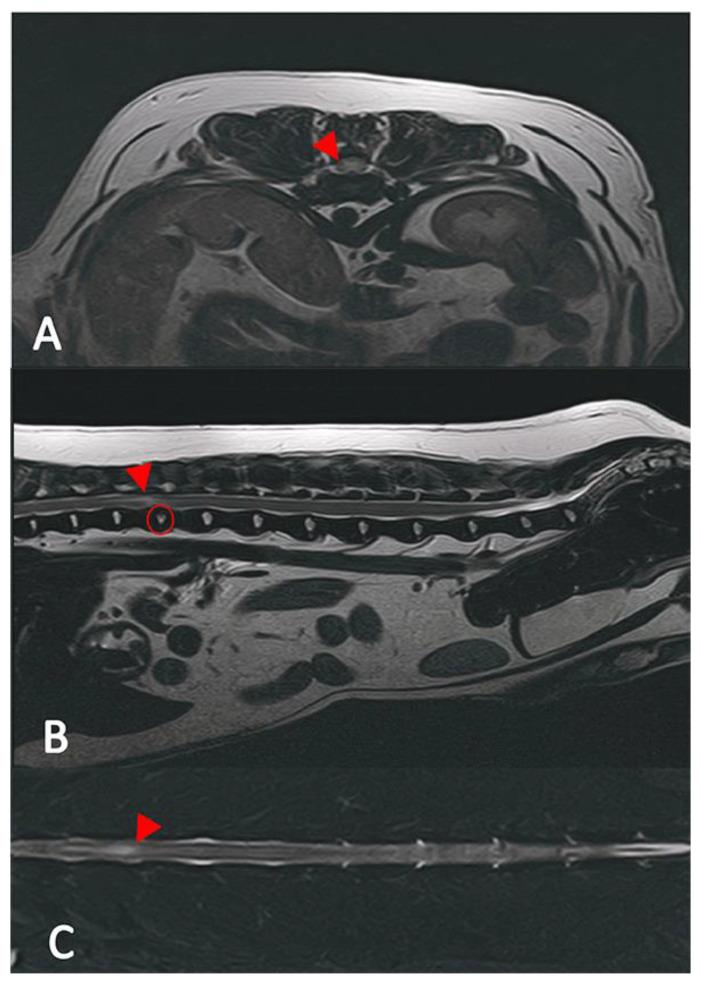

This retrospective study aims to investigate whether dogs with a contusive and dogs with a compressive intervertebral disc disease share comparable outcomes and prognoses when presenting with the same neurological grade. A total of 50 dogs with IVDE (compression group) and 45 dogs with ANNPE (contusion group) were included in this study. The protocol involved a thorough review of the medical records and CT/MRI images of the included dogs. Data encompassing signalment, initial clinical signs, post-diagnosis treatment and short-term outcomes (less than 8 months) were collected from the patient records. Information on long-term outcomes (more than 8 months) was obtained through interviews with the owners. Dogs in the compression group displayed clinical signs at a statistically significant younger age and were more likely to experience deteriorating neurological deficits compared to the contusion group. Conversely, dogs with contusions had a significantly higher incidence of external trauma history and vocalization at the onset of clinical signs. In both groups, the most affected spinal cord segment was T3-L3. The overall recovery rate to regain independent ambulation was 71% in the contusion group vs. 80% in the compression group. While some of the examined parameters revealed differences, most did not significantly differ between the groups.

这项回顾性研究旨在调查患有压迫性和挫伤性椎间盘疾病的犬只在呈现相同神经学分级时是否具有相似的结果和预后。本研究共纳入了50只患有椎间盘突出症(压迫组)的犬只和45只患有急性非化脓性神经炎(挫伤组)的犬只。该方案包括对纳入犬只的病历和CT/MRI图像进行全面审查。从患者记录中收集了包括信号特征、初始临床症状、诊断后治疗和短期结果(少于8个月)的数据。通过与犬主访谈获得了长期结果(超过8个月)的信息相较挫伤组,压迫组的犬只在统计学上更年轻的时候就出现了临床症状,并且更有可能出现神经功能缺损恶化的情况。相反,患有挫伤的犬只在临床症状出现时,有外部创伤史和发声的发生率显著更高。在两组中,受影响最严重的脊髓节段均为T3-L3。挫伤组恢复独立行走的总体恢复率为71%,而压迫组为80%。虽然一些检查参数显示出差异,但大多数参数在两组之间并无显著差异。